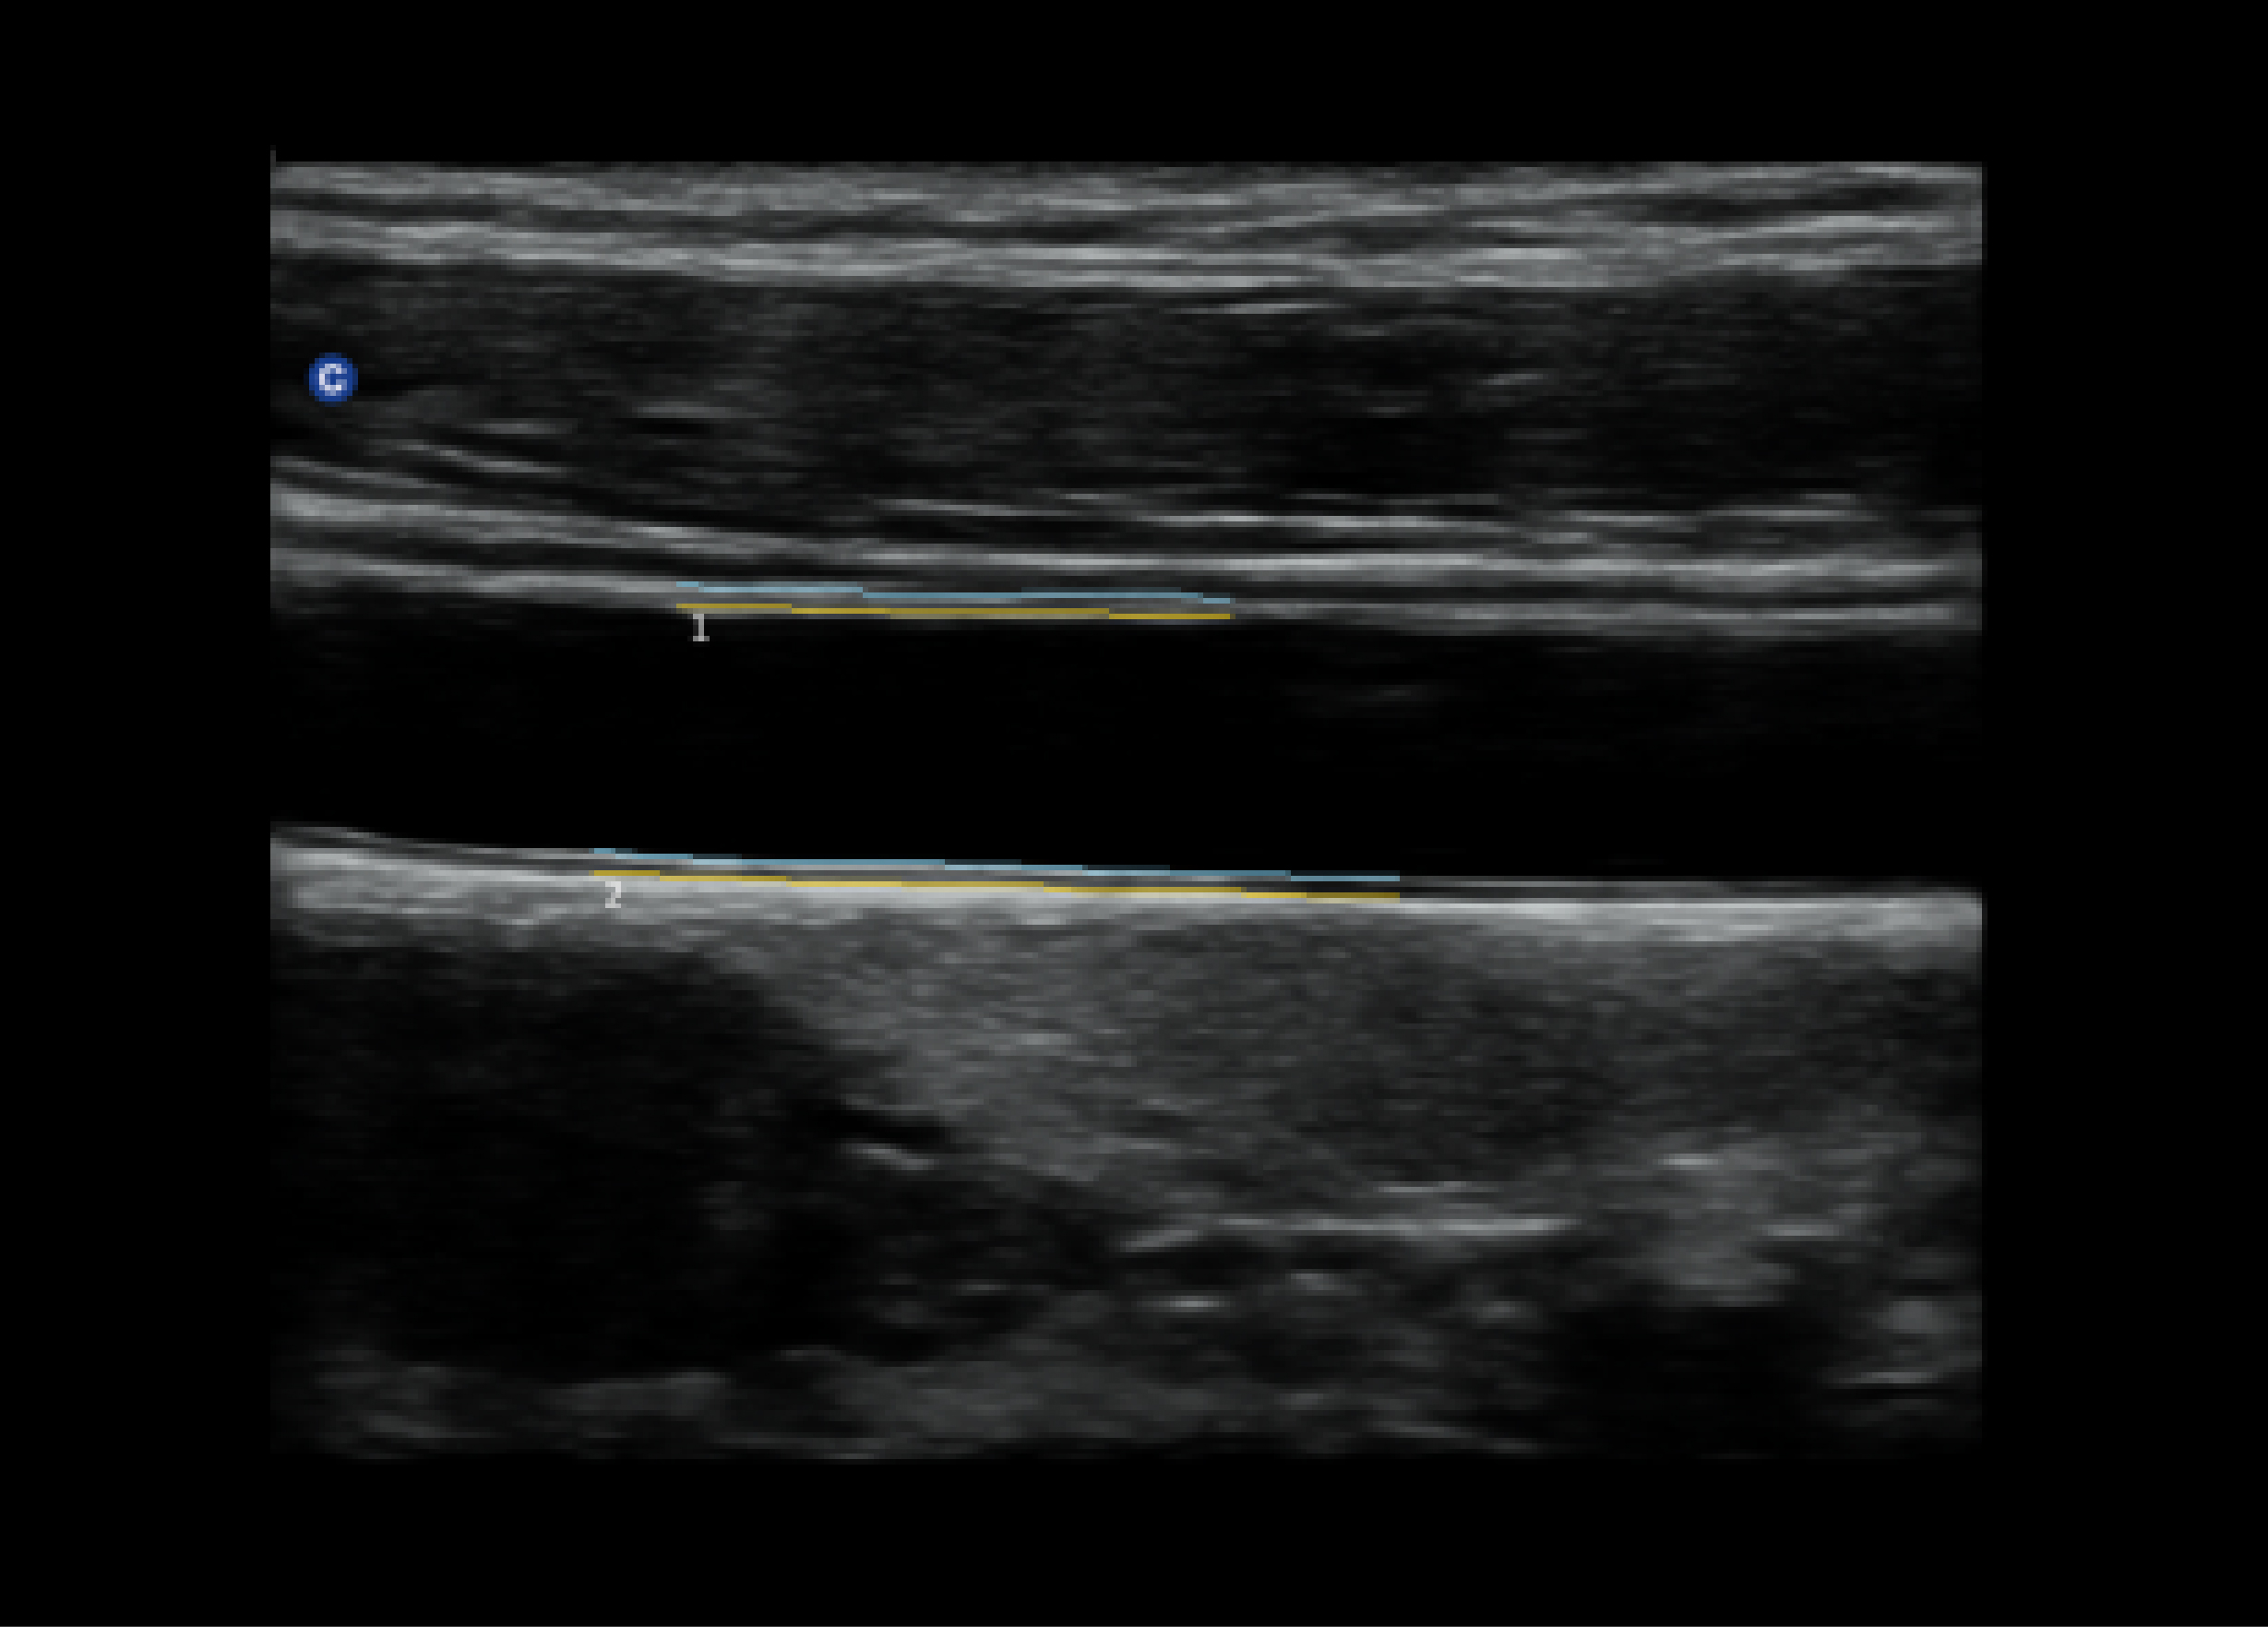

测量内膜厚度,在一个清晰的有内膜的B模式图像上,使用此功能,系统将会计算内膜的厚度并显示在屏幕上。